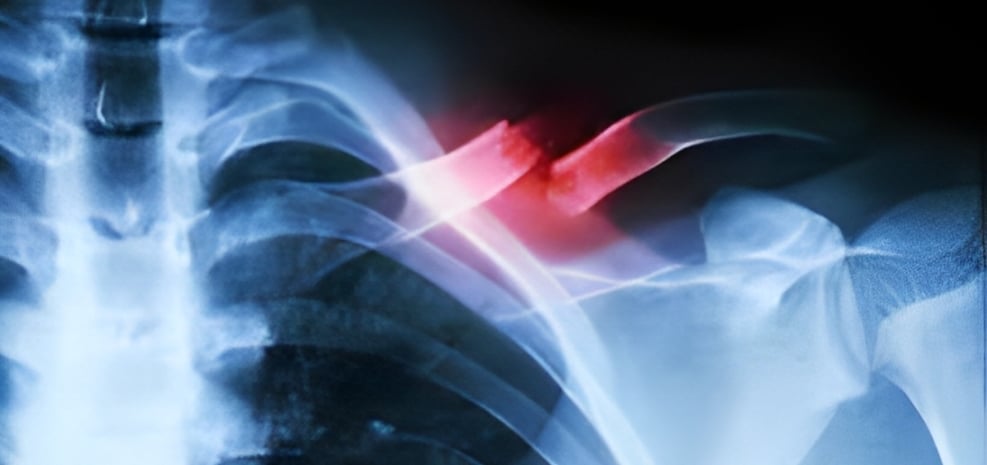

Fractures and Bone Injuries

X-ray imaging is the first-line diagnostic tool for detecting bone fractures and other injuries to the skeletal system. A simple x-ray can determine the location, type, and extent of a fracture, enabling doctors to make decisions on treatment, whether that’s casting, surgery, or other forms of intervention.

Trauma and Emergency Care

For patients with traumatic injuries, x-rays are often used in the ER to quickly identify fractures, dislocations, and other injuries. For instance, in cases of trauma, a chest x-ray may be performed to assess for collapsed lungs, rib fractures, or internal bleeding. The ability to diagnose these conditions rapidly can save lives by ensuring the right treatment is administered immediately.